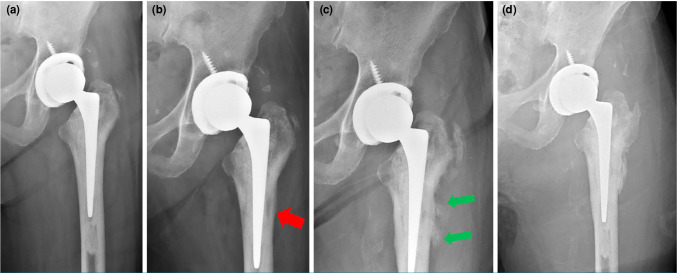

假体周围关节感染(PJI)仍然是全髋关节置换术(THA)后的一个具有挑战性的并发症,通常通过两阶段翻修来管理,这可能导致显著的发病率。在这篇文章中,我们提出一个罕见的病例肠炎沙门氏菌PJI,最初表现为假体髋关节脱位。术前使用血培养瓶进行髋关节抽吸可以早期识别细菌并指导靶向抗菌治疗。患者使用固定良好的定制关节间隔器(CUMARS)结构进行翻修THA,并使用靶向抗生素骨水泥。一年的随访表明感染成功根除,植入物固定稳定,功能预后良好。总之,该病例强调了诊断髋关节抽吸的重要性,并强调了CUMARS技术作为治疗由肠炎沙门氏菌等非典型生物引起的罕见PJIs的有效和持久解决方案的潜力。

Periprosthetic joint infection (PJI) remains a challenging complication following total hip arthroplasty (THA), commonly managed through a two-stage revision which can lead to significant morbidity. In this article, we present a rare case of Salmonella enteritidis PJI, initially presenting as prosthetic hip dislocation. Preoperative hip aspiration utilizing blood culture bottles enabled early identification of the organism and guided targeted antimicrobial therapy. The patient underwent revision THA using a well-fixed custom-made articulating spacer (CUMARS) construct, with targeted antibiotic-loaded bone cement. One-year follow-up demonstrated successful eradication of the infection, stable implant fixation, and good functional outcomes. In conclusion, this case underscores the importance of diagnostic hip aspiration and highlights the potential of the CUMARS technique as an effective and durable solution for managing rare PJIs caused by atypical organisms such as Salmonella enteritidis.